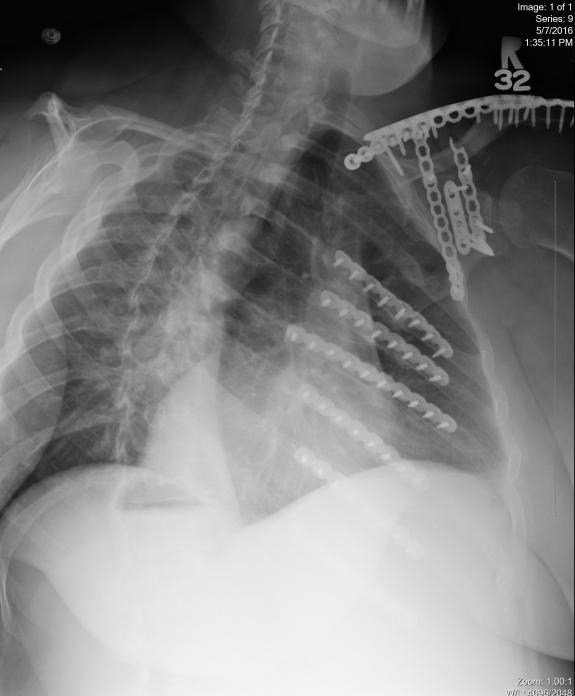

Today marks a milestone in the life of myself and my family. Today is the 11th-year survivor-versary of the wreck that, in part, changed the course of all of our lives.

While it remains factual that it was myself and our youngest son involved in the actual wreck itself all those years ago, the family as a whole would become and remain affected as a result of its aftermath – for years to come.  The rehabilitation journey has not been for the faint of heart and continues…albeit in different ways now than when it all began.